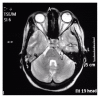

Renal cell carcinoma (RCC) has unusual presentation affecting elderly males with a smoking history. The incidence of RCC varies while the incidence of spread of RCC to the clivus is rare. The typicality of RCC presentation includes hematuria, flank pain, and a palpable flank mass; however, RCC can also present with clival metastasis. The unique path of the abducens nerve in the clivus makes it susceptible to damage in metastasis. We report a case of a 54-year-old African American female that was evaluated for back pain, weakness, numbness, and tingling of bilateral lower extremities and subsequently disconjugate gaze and diplopia. Brain MRI confirmed metastasis to the clivus. She was started on radiotherapy and was planned for chemotherapy and transfer to a nursing home. When a patient presents with sudden unusual cranial nerve pathology, the possibility of metastatic RCC should be sought.